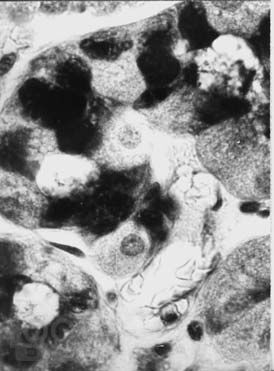

В небольшой по объему монографии представлена краткая анатомо-гистологическая характеристика нормальной слизистой оболочки желудка и двенадцатиперстной кишки, рассматривается морфологическая классификация гастритов и гастропатий, а также сущность дистрофических, воспалительных и дисрегенераторных изменений слизистой оболочки желудка при различных формах гастродуоденальной патологии. Приводятся краткие сведения об основных правилах гистологической техники, знание которых необходимо клиницисту. Основная цель пособия — дать молодому врачу представление об основах морфологической диагностики заболеваний желудка. Книга также может быть полезной для первичного образования и совершенствования гастроэнтерологов, клинических морфологов, эндоскопистов, а также для врачей других специальностей.